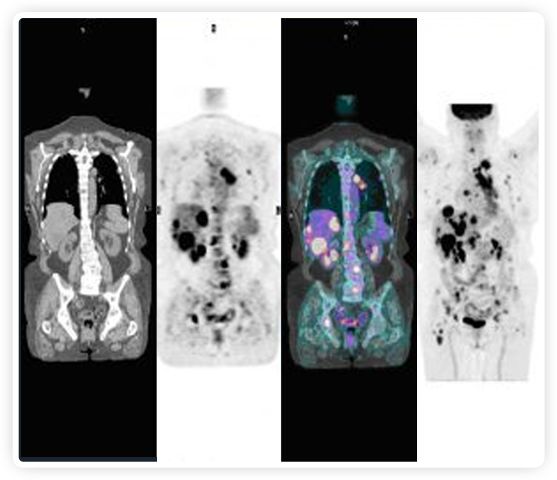

正電子發(fā)射斷層掃描(PET)是癌癥檢測中已建立的成像標準,與其他成像方式相比,PET能提供高靈敏度和特異性的圖像。

到目前為止,放射腫瘤學中(使用的圖像主要是結構性的,而PET圖像可以提供生物學信息。通過使用注射示蹤劑,例如18-FDG,PET可以描繪腫瘤的代謝活性,使其“點亮”。(FDG是用于可視化癌癥代謝的最廣泛使用的示蹤劑。與正常組織相比,腫瘤細胞保留更高水平的FDG。)不同的PET示蹤劑可以識別腫瘤的不同生物學特征,例如特定生物標志物抗原(例如,PSMA)或甚至探測免疫系統(tǒng)本身(例如,PDL1表達或活化的T細胞)。

PET+放療共同治療

RefleXion將PET成像與立體定向放射治療相結合。在注射示蹤劑后,RefleXion的技術基于示蹤劑信號實時地在一個或多個目標上引導治療性X射線。使用這種專有方法,RefleXion的平臺有可能比現(xiàn)有系統(tǒng)向癌癥病變提供更高劑量的輻射,并改善周圍健康組織的保護。